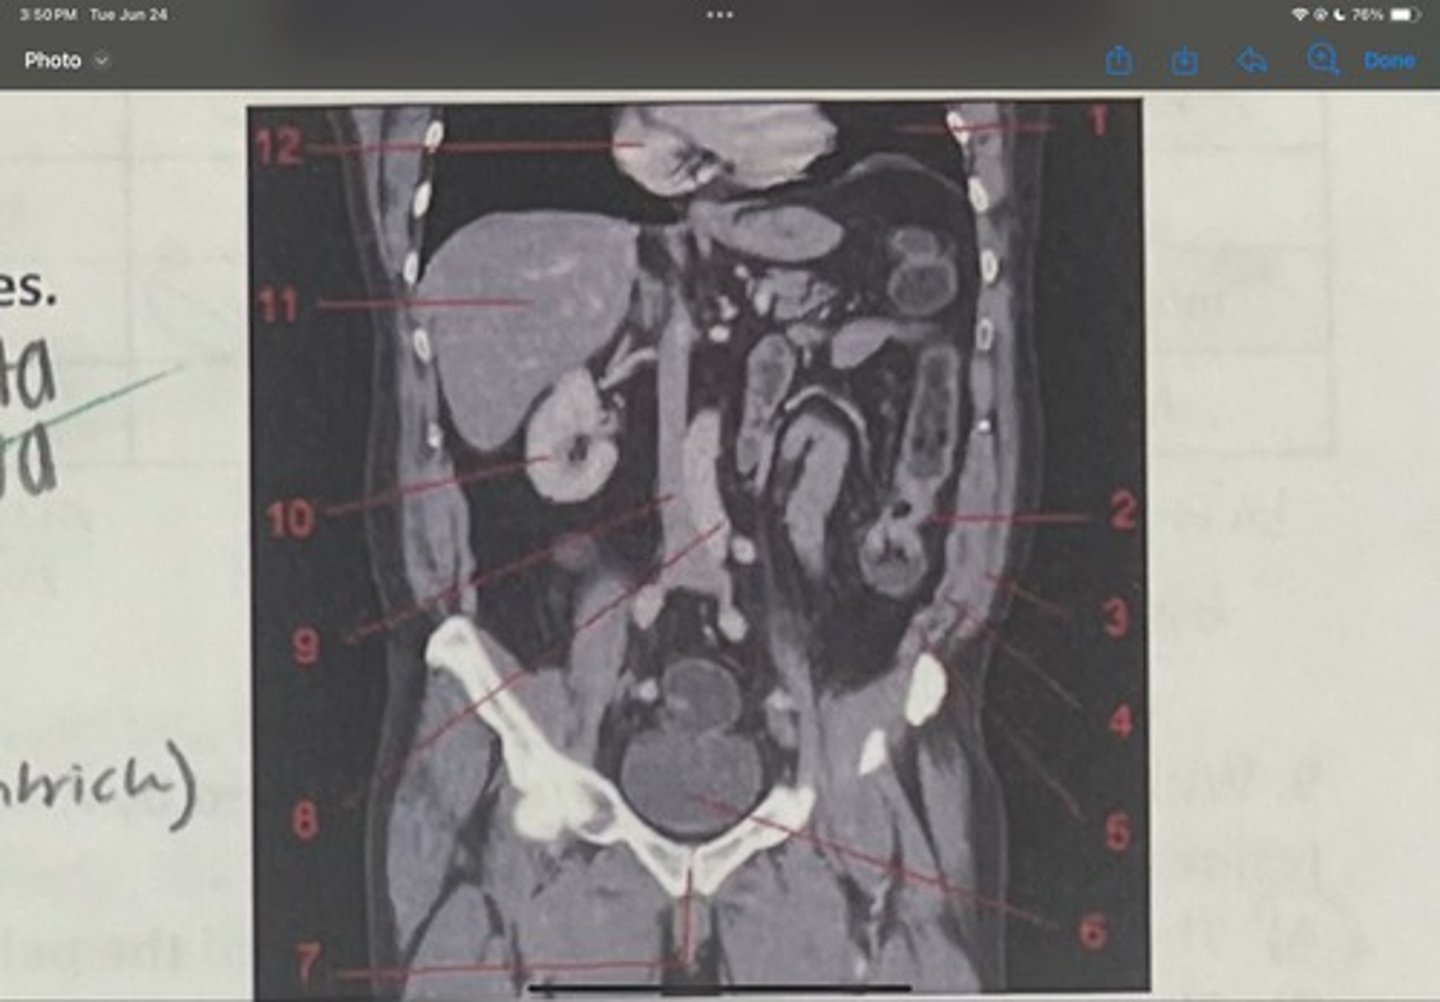

What is 1

Descending colon

What is 2

External oblique

What is 3

Internal obliques

What is 4

Transversus abdominis

What is 5

Bladder

What is 6

Pubic sysmphysis

What is 7

Abdominal aorta

What is 8

Inferior vena cava

What is 9

Right kidney

What is 10

Liver

What is 11

Heart (right ventricle)

What is 12

Subcostal nerve (T12)